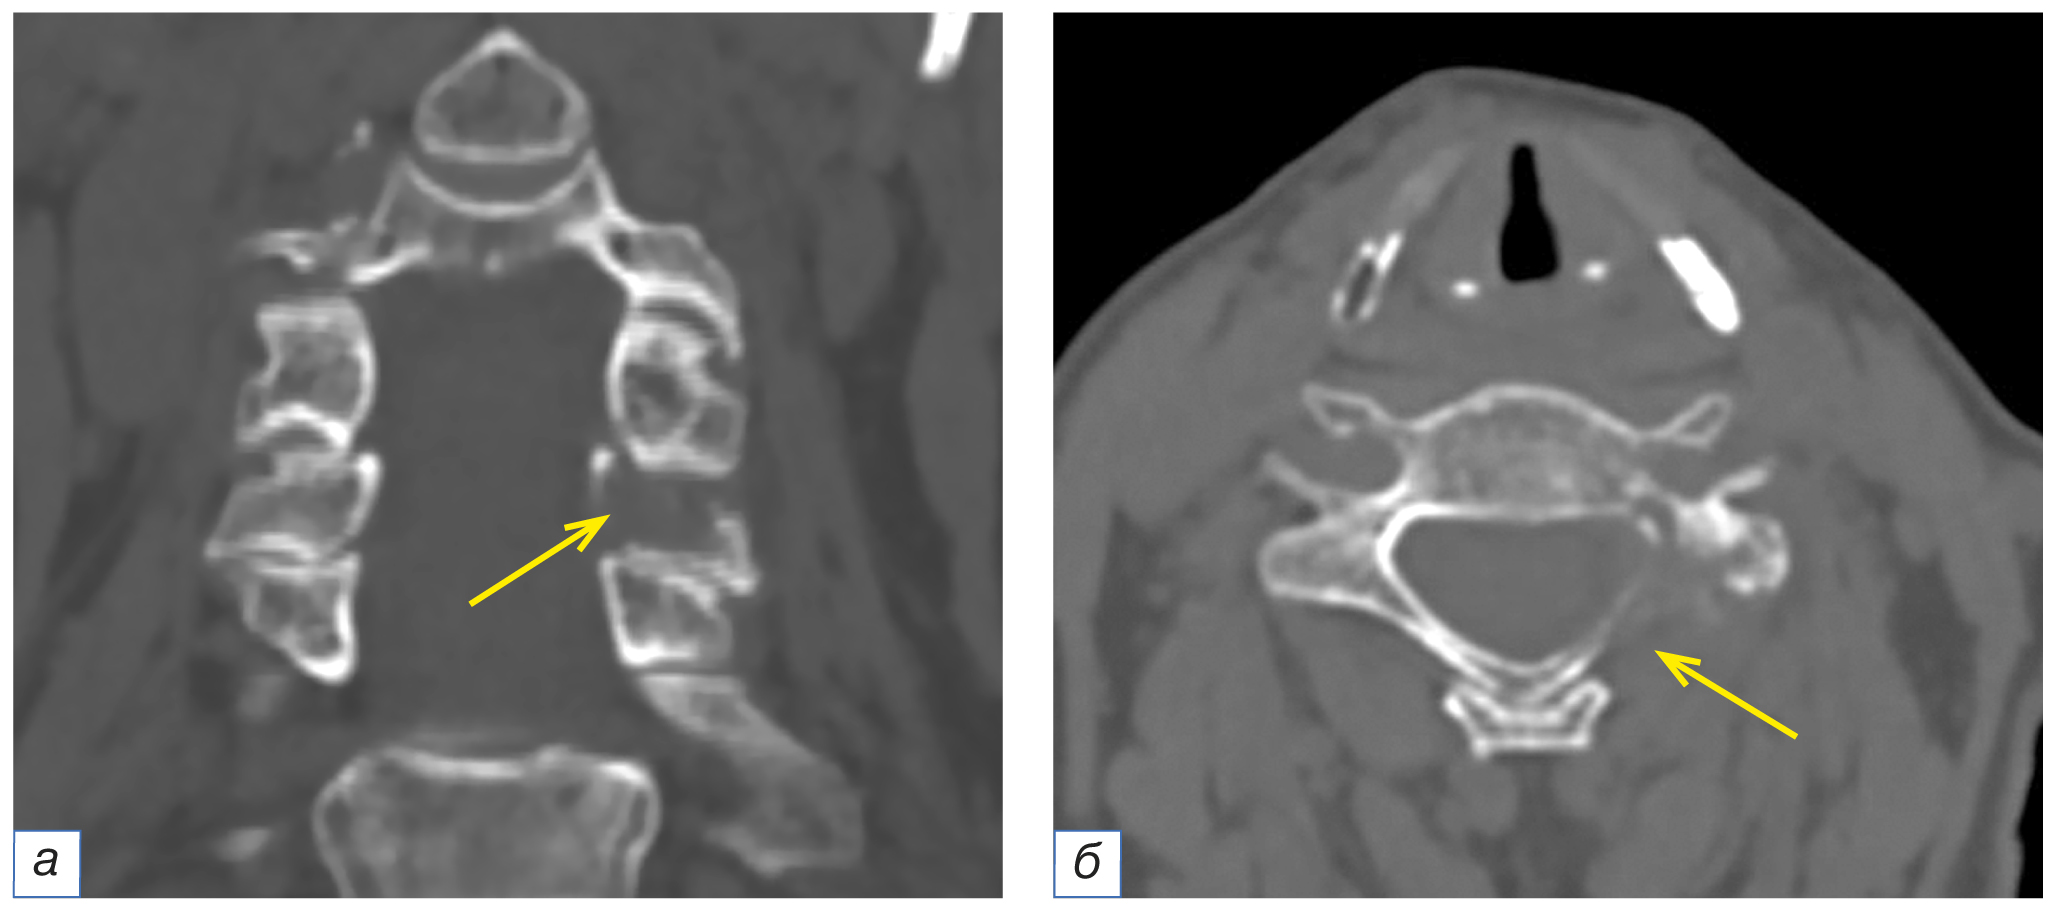

Рис. 6. Компьютерные томограммы области головы и шеи во фронтальной (а) и аксиальной (б) плоскостях. У пациентки в возрасте 67 лет с фолликулярным раком щитовидной железы определяется остеолитический очаг деструкции в левой дужке позвонка С6 (жёлтые стрелки).

Fig. 6. Computed tomograms of the head and neck, coronal (а) and axial (б) planes. A 67-year-old patient with follicular thyroid cancer has an osteolytic focus of destruction in the left arch of the C6 vertebra (yellow arrows).